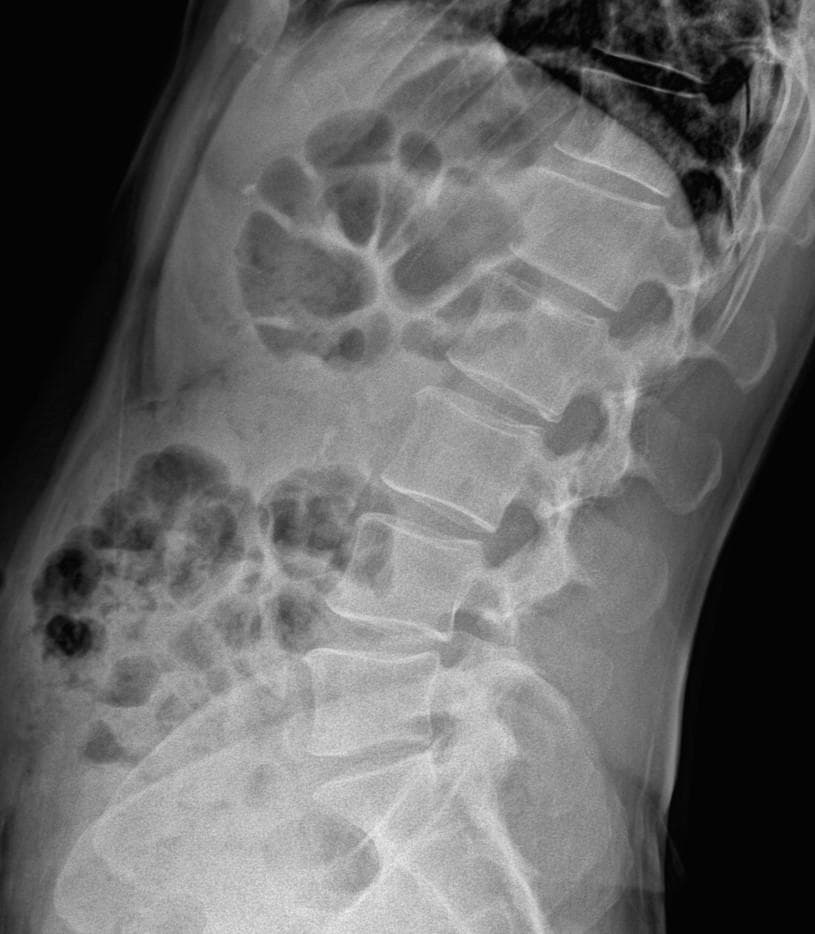

허리랑 고관절 엑스레이사진판독 조언 부탁드립니다

간헐적인 약간의 찌릿 뜨끔 한 오른쪽허리통증이 근한달정도

허리를 굽힌다던지등의 특정자세에 오는것 같진 않습니다

최근 한몇일은 일시적 뻐근한 느낌도 있고요

엑스레이 상에서는 요추 배열이 전반적으로 잘 유지돼 보입니다. 마나 일부 요추 간격이 좁아진 부위가 있어 보입니다. 말씀하신 것처럼 특정 동작에서 찌릿 혹은 뜨끔하거나, 최근 뻐근함이 생기는 건 디스크 초기나 근육, 인대 긴장에서도 나타날 수 있습니다.

허리의 커브가 줄어들어있다는것을 제외하고는 크게 문제가될만한 부분은없는데요 통증과불편감이 지속된다면 MRI와같은 정밀검사가 필요할수있습니다

사진상 요추 사이의 간격이 다소 좁아 보이며 간격이 좁다는 것은 퇴행성 변화를 의미하며 척추의 정렬 또한 큰 전위는 없어 보이나 허리 곡선이 정상보다는 조금 감소한 상태로 이러한 경우 근육의 긴장이나 만성적인 통증이 발생할 수 있습니다.

• 엑스레이 검사를 통해서는 현실적으로 뼈 위주의 평가만 가능하며 정밀하고 자세하게 평가를 내리는 것은 어렵습니다. 올리신 엑스레이 사진들에는 특별히 문제가 있다고 볼만한 소견이 크게 있어보이거나 하지는 않습니다.

우선 현재로썬 척추와 척추 사이인 디스크 공간이 좁지는 않아보이지만 다소 요추의 커브가 감소되어 있어 보입니다.